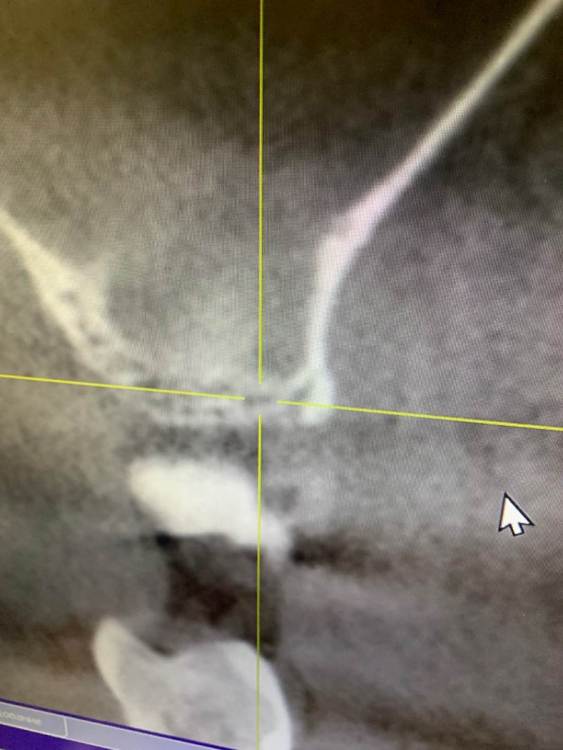

KOCTb Опубликовано 1 января, 2024 Поделиться Опубликовано 1 января, 2024 Здравствуйте коллеги. Может кто-то подскажет полезного. Пациентка. Лет 6 назад пришла с симптоматикой пульпита во втором секторе. На некоторых зубах были пломбы, без криминала. Зубы были проверены на витальность. Все живые. Пальпаторно передняя стенка ВП давала лёгкую чувствительность. Сделали КТ. Апикальных изменений не выявлено, а в пазухе слева признаки гайморита. Заполнена была бальше чем наполовину. Отправил к ЛОРу. Пролечили. Анатомическое строение не очень понравилось. С тех пор каждую зиму у неё обострение ВЧ синусита слева. Иногда даже два раза бывает. Каждый раз ЛОР в направляет к стоматологу и говорит, что гайморит одонтогенгый. Врачи рентгенологи в описании иногда там находят одонтогенгую кисту… Года два назад пациентка сходила поменяла все пломбы, на всякий пожарный. Со слов зубы все были витальные при лечении. Ну и собсвенно опять ВЧ синусит. Смущает анатомическое строение между 25 и 26 зубом. Не может ли там через периодонтальную щель «сифонить» ? Говорит между зубами иногда какой-то дополнительный дискомфорт есть. Ссылка на комментарий

Astronaft Опубликовано 14 января, 2024 Поделиться Опубликовано 14 января, 2024 Здравствуйте. 6 лет назад: подробнее про симптомы пульпита? как полечили гайморит и чего добились? Анатомия действительно интересная. Интуитивно, или естественная впадина которая способствует застою либо проблемы в соустье вызывают застой и кислотный секрет лизирует самое слабое место. Опять же интуитивно, пациентке приказать зубы не трогать, не ходить выискивать проблемы. Очень подробно расспросить анамнез, в том числе что помогает, что запускает синусит. Если соустье открыто то я бы рекомендовал регулярно промывать физраствором с ЭДТА и выждать. Ссылка на комментарий

KOCTb Опубликовано 15 января, 2024 Автор Поделиться Опубликовано 15 января, 2024 19 часов назад, Astronaft сказал: Здравствуйте. 6 лет назад: подробнее про симптомы пульпита? как полечили гайморит и чего добились? Анатомия действительно интересная. Интуитивно, или естественная впадина которая способствует застою либо проблемы в соустье вызывают застой и кислотный секрет лизирует самое слабое место. Опять же интуитивно, пациентке приказать зубы не трогать, не ходить выискивать проблемы. Очень подробно расспросить анамнез, в том числе что помогает, что запускает синусит. Если соустье открыто то я бы рекомендовал регулярно промывать физраствором с ЭДТА и выждать. Здравствуйте. Ну как обычно пульпитная симптоматика при ВЧ синусите. Разлитые периодические боли в верхнем секторе, с непонятной локализацией. Пальпаторно передняя стенка ВЧ пазухи давала болезненность. От 25 до 27 зуба. На КТ зубов затенение в ВЧ пазухе. Отправил тогда к ЛОРу. Подробности лечения у ЛОР врача тогда не знаю. Синуситы в холодное время года. Соустье пародонтальным зондом не выявлено. Носо-ротовая проба также отрицательная. Но тут и понятно если и есть ход, то крайне мизерный. Там слизистой завалено всё. Ссылка на комментарий